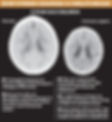

If we take a closer look at the scans of a brain that is "normal" vs one that has experienced extreme neglect, it paints a clear description of how prolonged neglect and abuse creates lasting damage to the brain. This is not to say every child will be affected in this way, but there is higher likelihood the longer the abuse occurs and the less secure the attachment.

The effect of trauma literally rewires the brain and nervous system. The brain can be smaller, areas such as the temporal lobes which are in charge of emotions and receiving input from senses can be shut off, and their nervous systems can be stuck on high alert even when they may no longer be in danger.